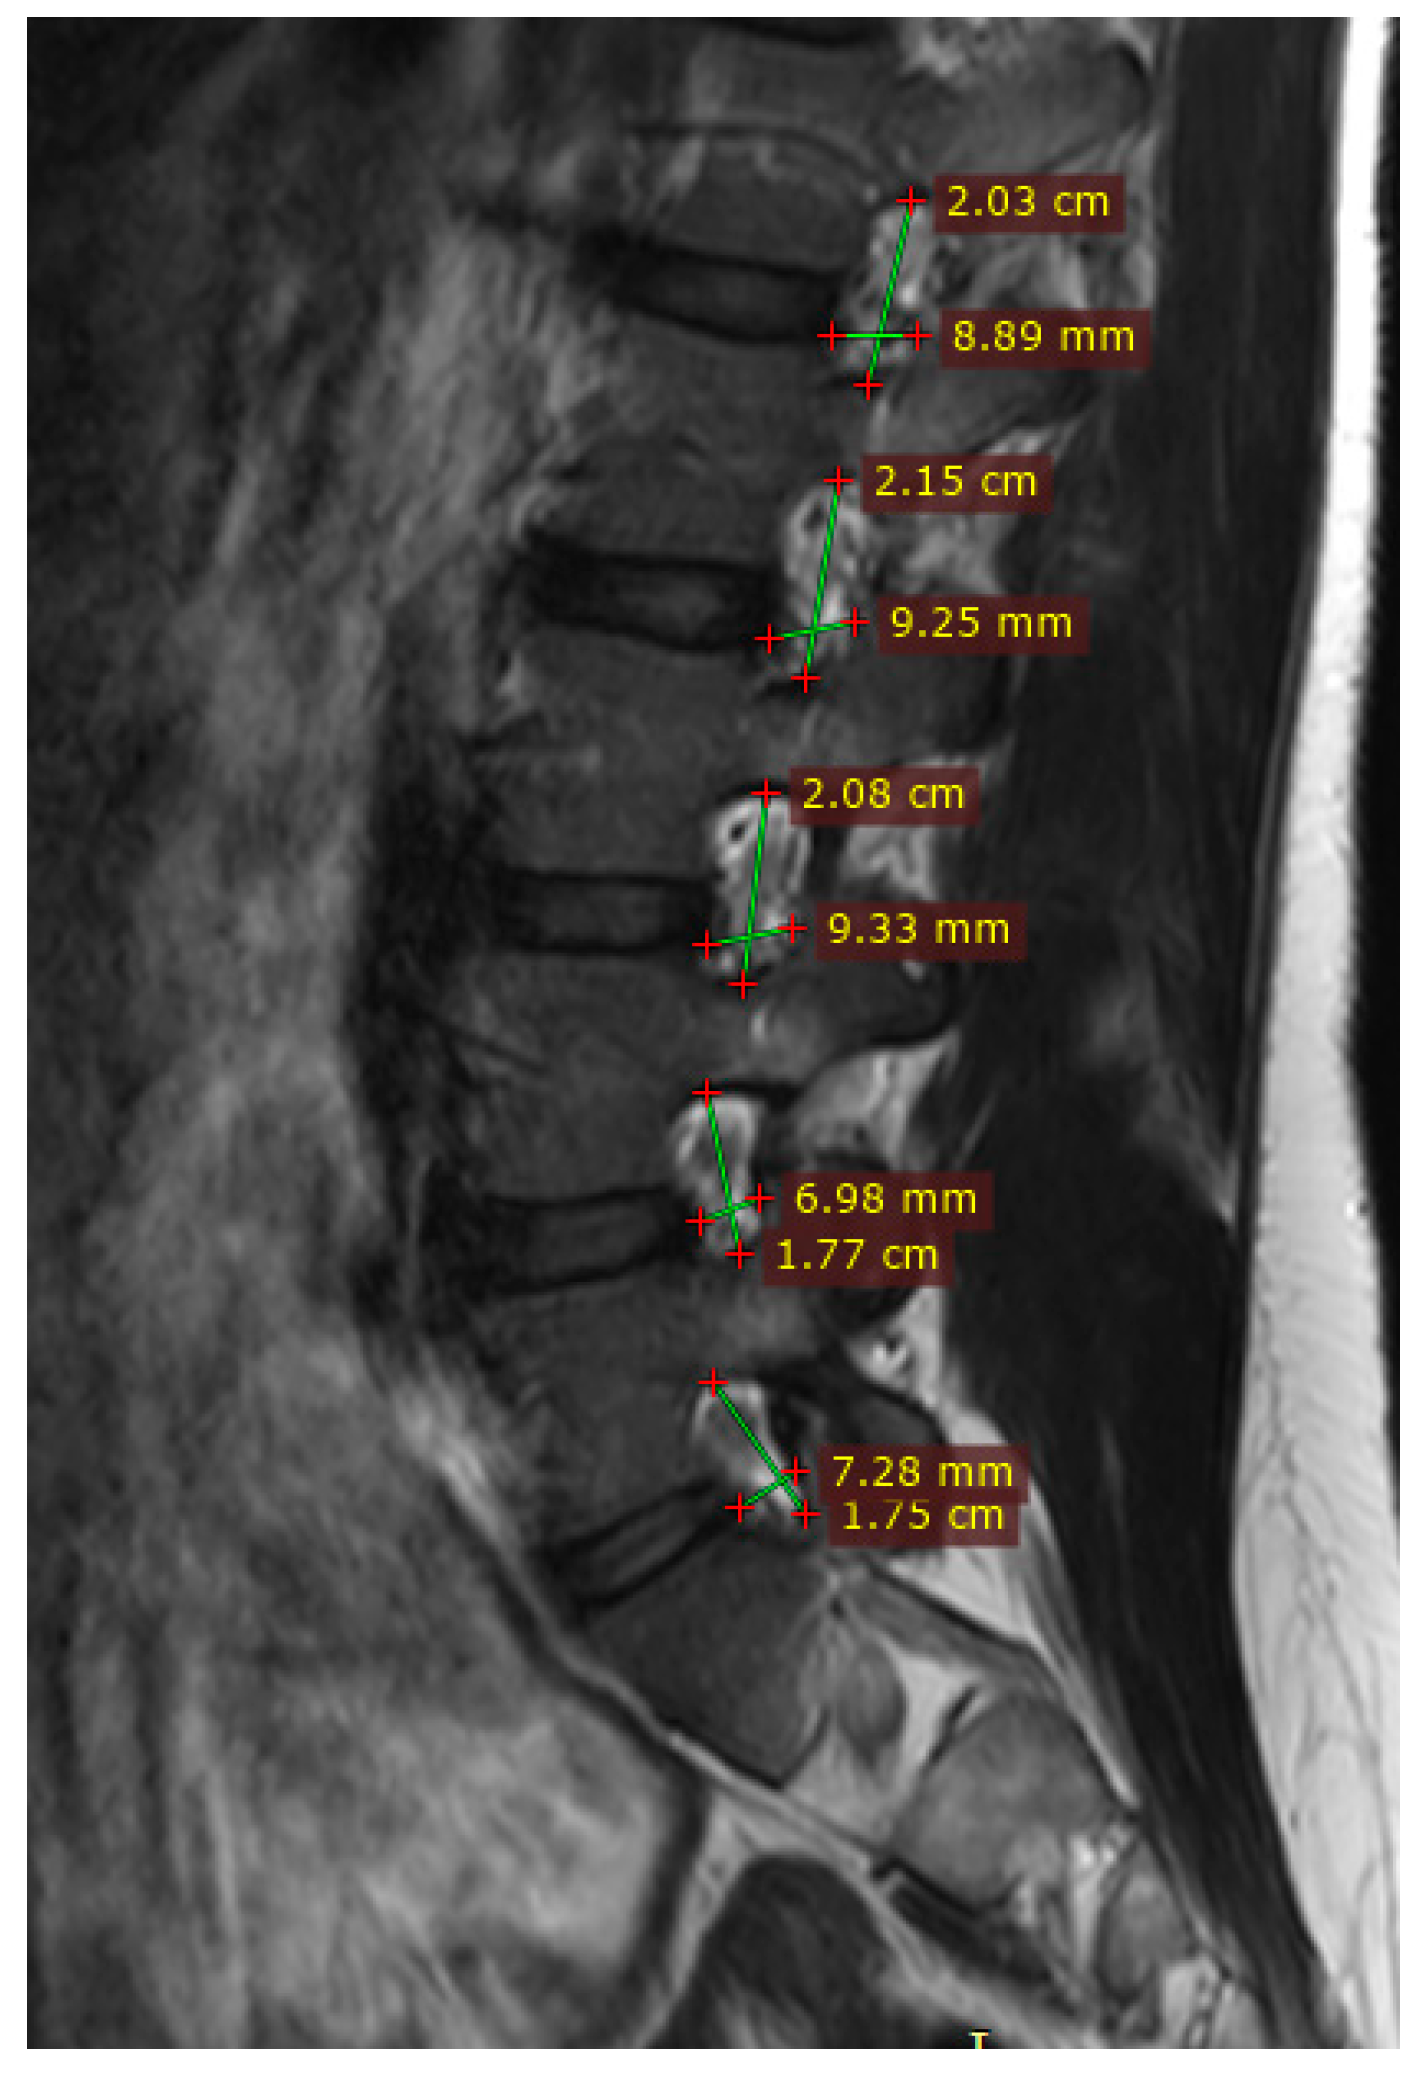

Magnetic Resonance Imaging (MRI)

2.7.1. Volumetric Analysis

3.1. Volumetric Analysis of Lumbar Foramina